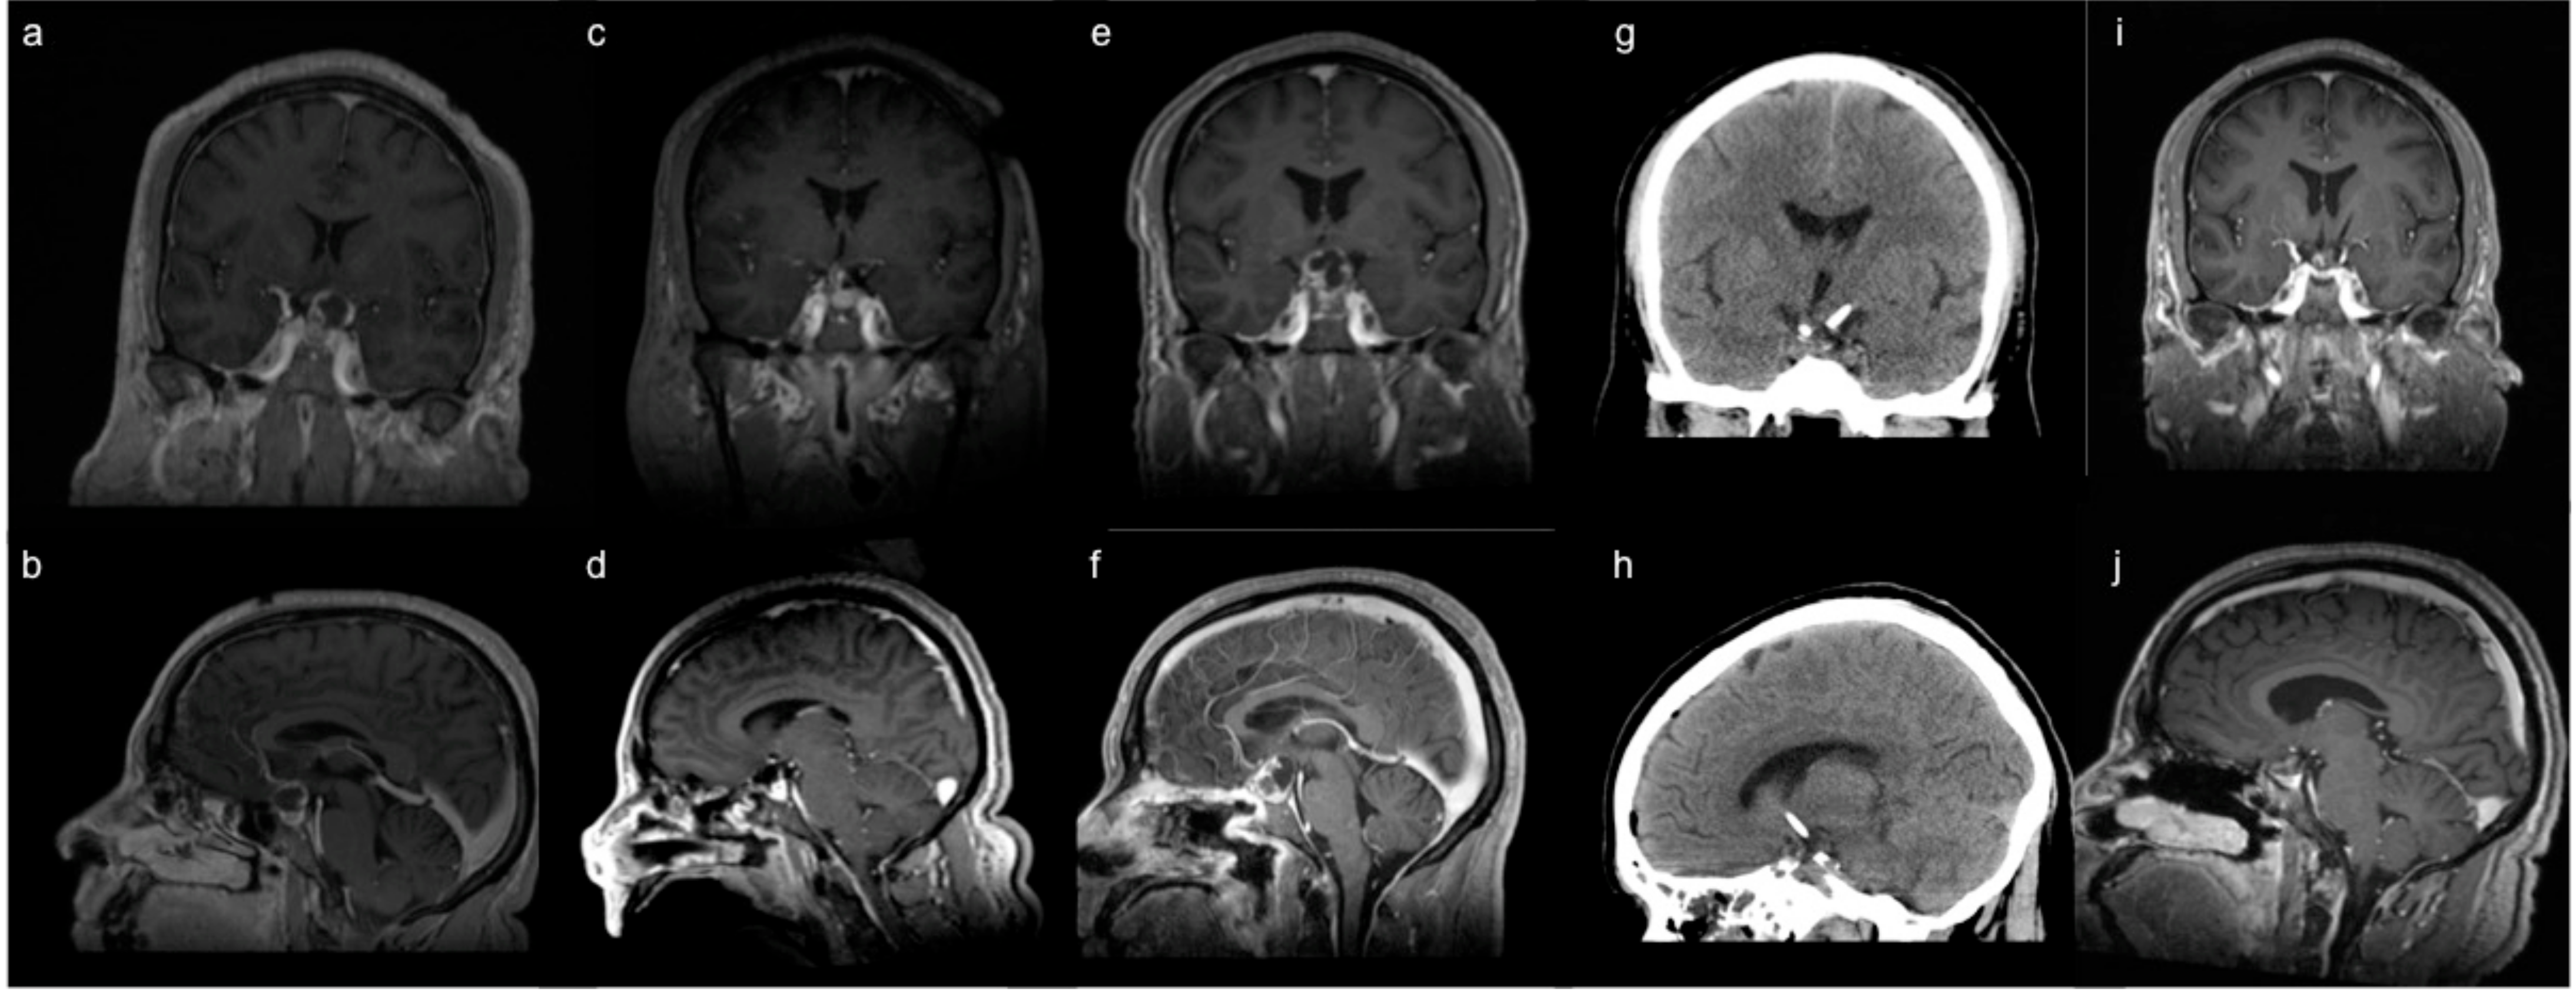

3.1. Endoscopic Endonasal Approach

3.2. Supraorbital Craniotomy

4. Adjunctive Treatment Modalities

4.1. Stereotactic Cyst Decompression

5. Overall Approach to Surgical Treatment